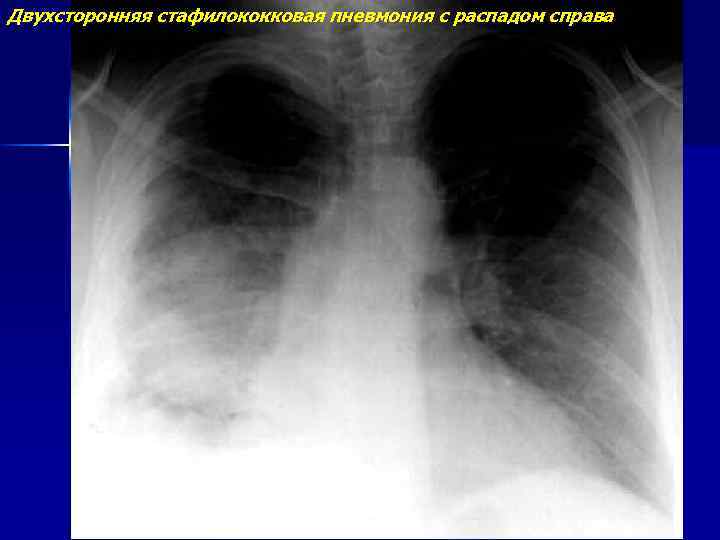

Стафилококковые и стрептококковые пневмонии

Двухсторонняя стафилококковая пневмония с распадом справа